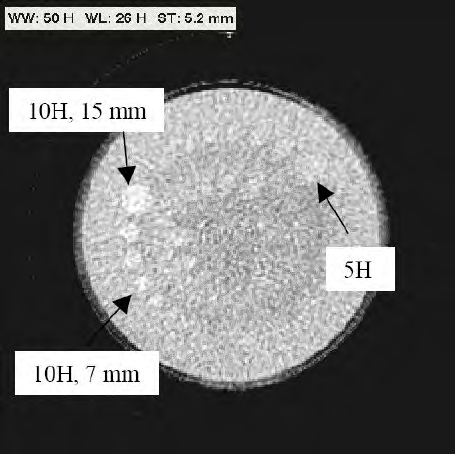

14.5 Tryb kontroli jakości przez użytkownika............................................................................... 255

14.6 Test werykacyjny użytkownika........................................................................................... 255

14.6.1 Test automatycznej kontroli ekspozycji................................................................256

14.6.2 Kontrola ograniczników wiązki.............................................................................256